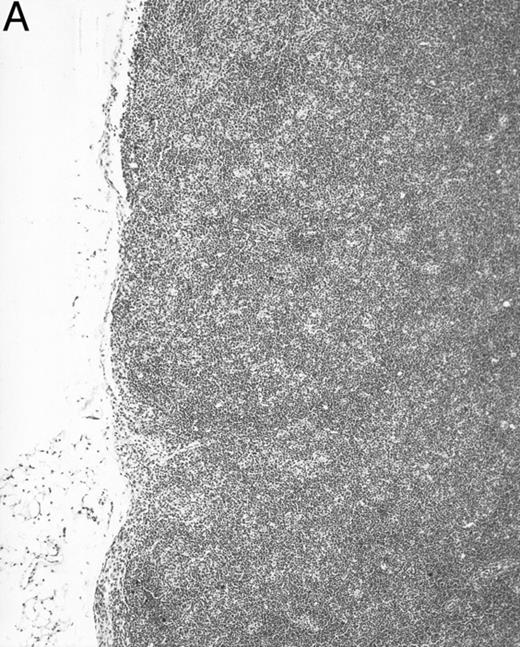

Histologic alterations occur in hematopoietic tissues of IFN-γ transgenic mice.Focal granulomatous lesions were seen in the bone marrow of many of the transgenic mice (Fig 4A) but not in control mice. These lesions were found to contain primarily Mac-2+ mononuclear cells (data not shown). In addition, the marrow cavities of IFN-γ transgenic mice contained residual degenerated cartilaginous masses in the metadiaphyseal (young) or diaphyseal (adult) parts primarily in long bones and ribs (Fig 4B). Moribund transgenic mice often had generalized or local secondary bacterial infectious lesions, including pyelonephritis, meningoencephalitis, endocarditis, bone marrow necrosis, arthritis, and uterine granulomas. Bacteria and bacterial colonies were often seen within the lesions.

Bone marrow alterations in IFN-γ transgenic mice. (A) Tibial bone marrow of a 3-month-old transgenic mouse showing granulomatous lesions (arrows) stained with H&E. The focal lesions were composed of clusters of histiocytes/macrophages (original magnification × 300; Bouin's fixed and paraffin-embedded section). (B) A rib of an 8-month-old transgenic mouse showing a cartilaginous mass in the marrow cavity attached to the cortical bone. Chondrocytes in the mass are degenerative. The mass is covered with a thin osseous layer. (Original magnification × 75; H&E; Bouin's fixed and paraffin-embedded section.)

Gross examination of animals at all ages studied showed that transgenic mice had much smaller spleens than those of normal littermates. Histologically, the white pulp areas in the spleens of transgenic mice were composed only of the periarteriolar lymphocytic sheaths (PALS), whereas the primary follicles and outermost marginal zones that typically contain B cells and surround the PALS were absent (Fig 5).

Spleen of a 6-month-old transgenic (A) and an age-matched control (B) mouse. White pulp of the transgenic mouse is composed only of lymphocytes in the PALS (arrows), whereas those areas in control mice are composed of primary follicle (f ) and marginal zone (m). (Original magnification × 75; H&E; Bouin's fixed and paraffin-embedded section.)